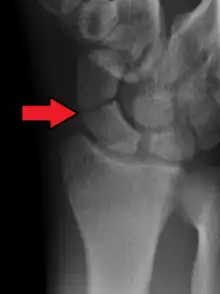

A subtle scaphoid fracture

A more obvious scaphoid fracture on a scaphoid view X ray

Radiolucency around a 12 days old scaphoid fracture that was initially barely visible.[13]